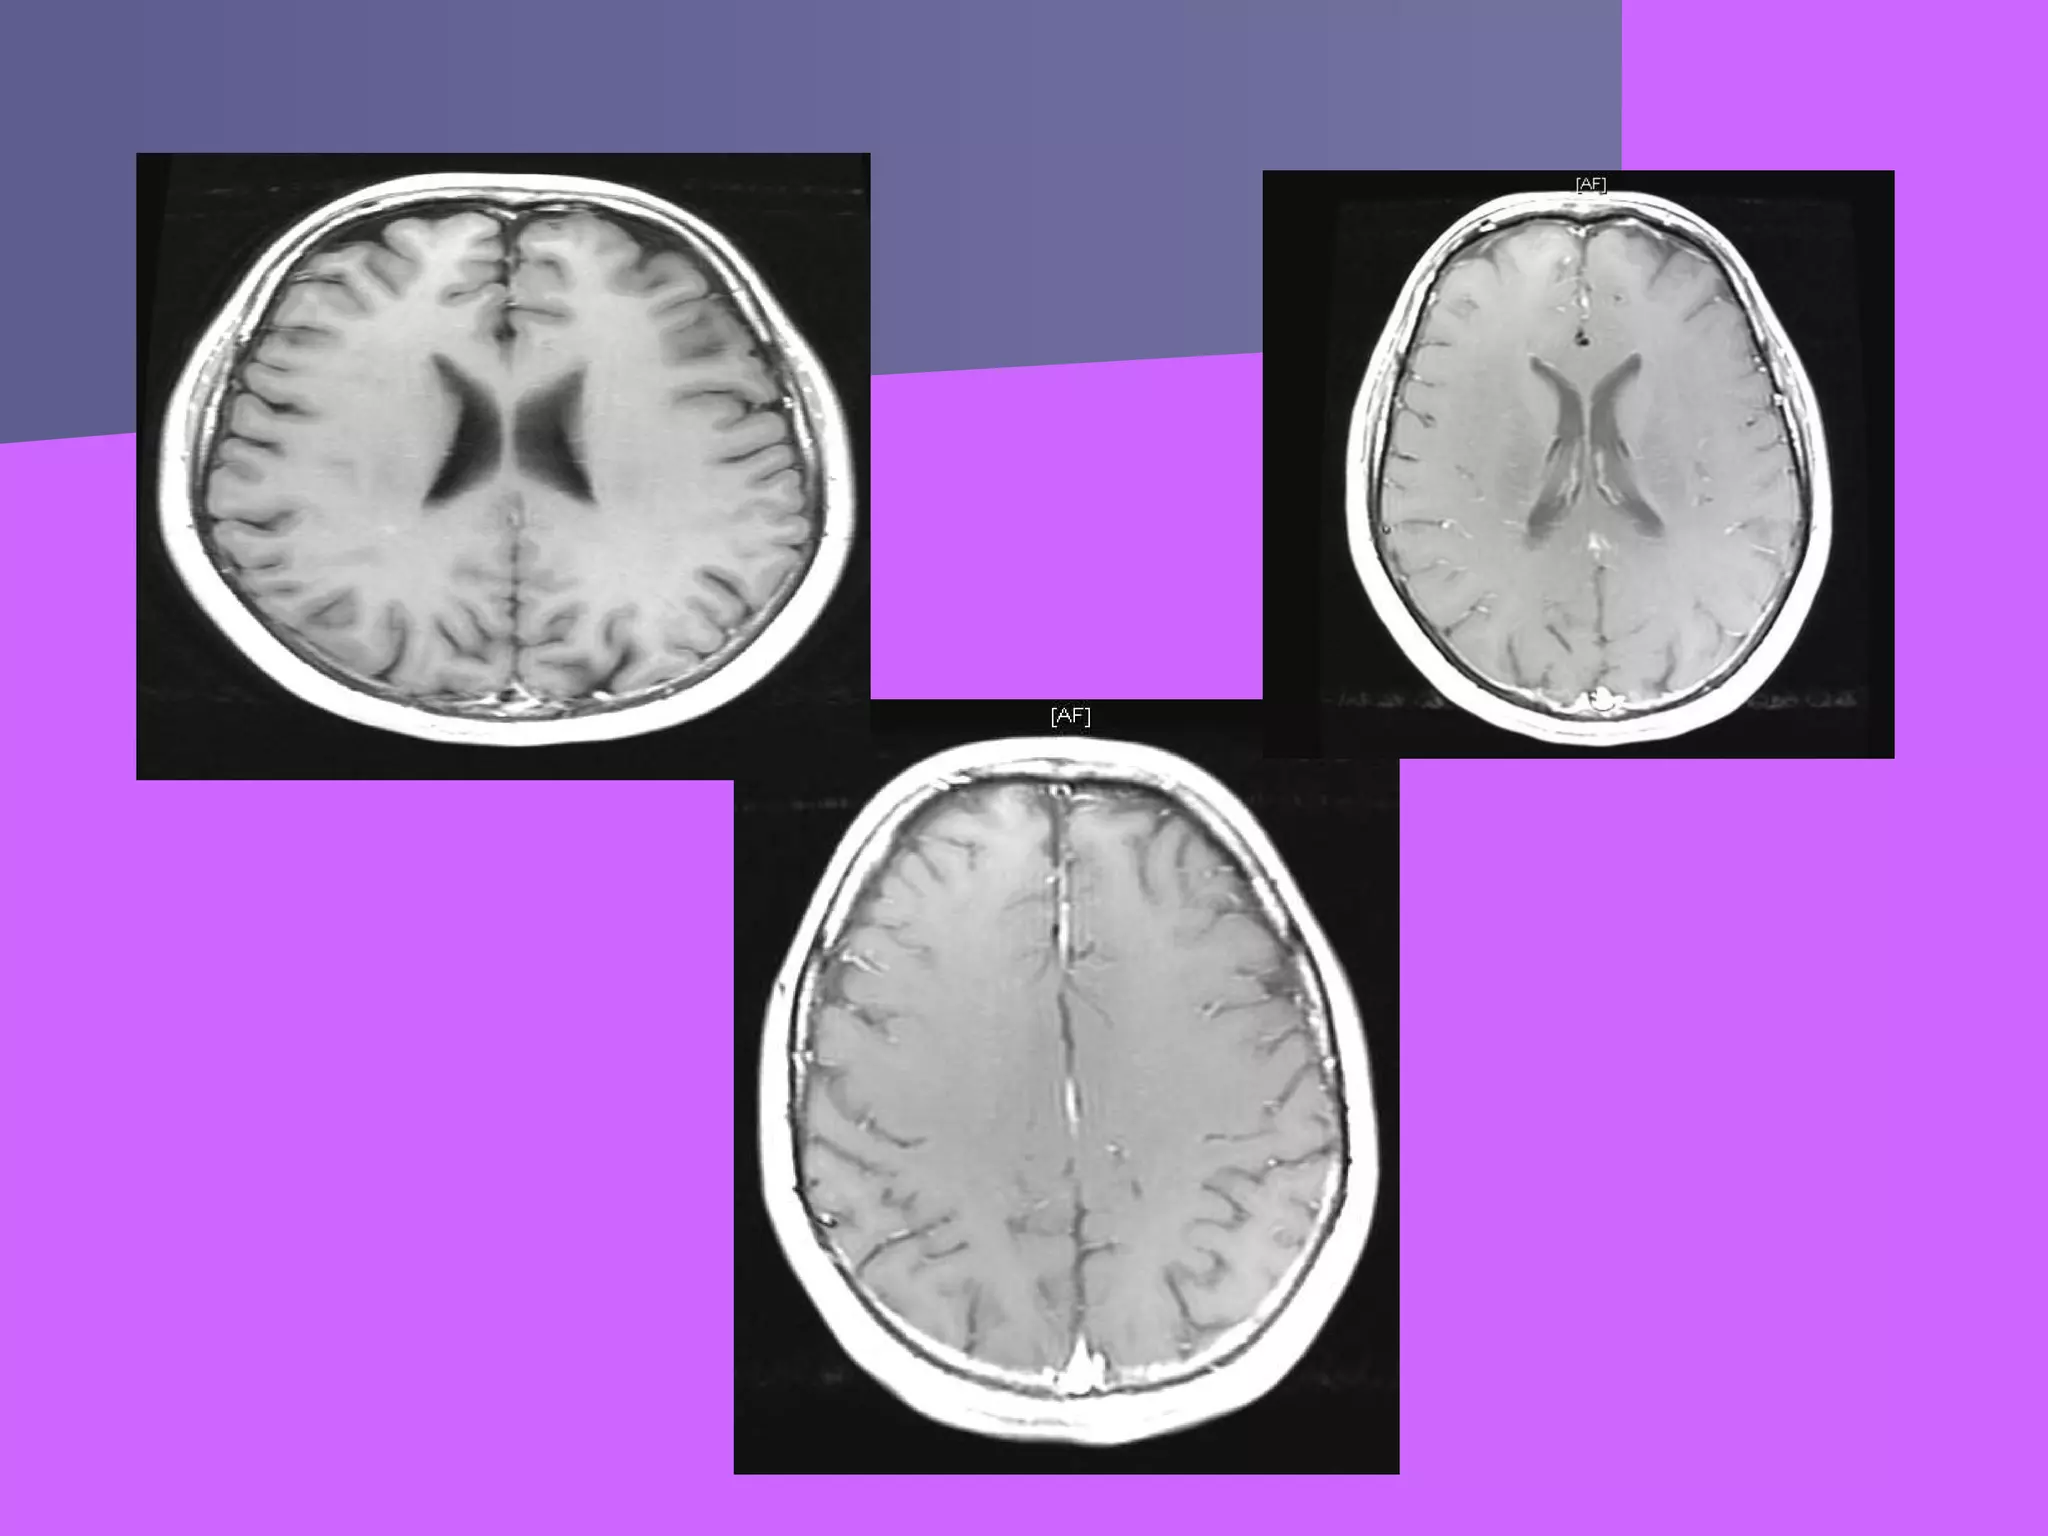

Будова головного мозку

Стовбур мозку

Стовбур мозковий

утворений

довгастим мозком,

мостом, мозочком,

ніжками мозку і

чотиригорбковим

тілом. Підкірковий

відділ – це

проміжний мозок і

підкіркові ядра

великих півкуль.

Стовбур мозку Стовбур мозковий утворений довгастиммозком, мостом, мозочком, ніжками мозку і чотиригорбковим тілом. Підкірковий відділ – це проміжний мозок і підкіркові ядра великих півкуль.